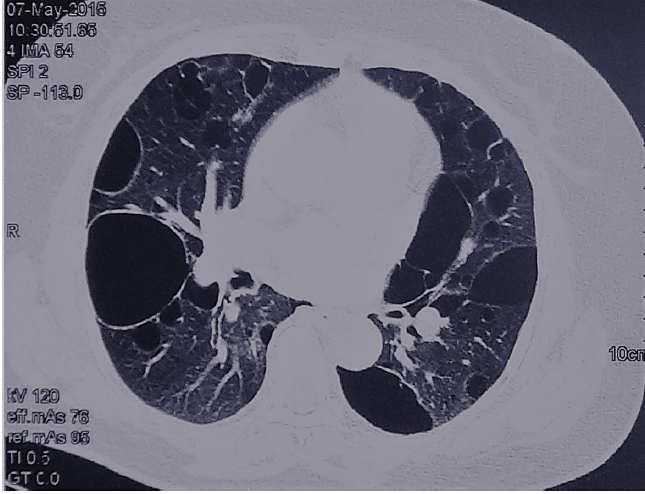

肺朗格汉斯细胞组织细胞增多症(PLCH)要注意囊和结节的特征,它囊性病变的囊壁相对较厚,还可能看到一些结节,所以我们如果看到不规则的、囊壁稍厚、有结节的、分布在中上肺的就一定要注意鉴别PLCH。下面两张影像分别提示我们要注意囊和结节、注意区域分布。

图:PLCH患者的影像,注意囊和结节

图:PLCH患者的影像,注意区域分布